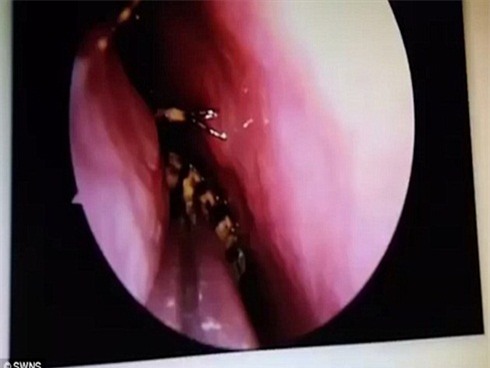

Để gắp được con gián ra khỏi hộp sọ của người phụ nữ, các bác sĩ đã phải sử dụng tới máy hút và nhíp trong ca phẫu thuật kéo dài 45 phút đồng hồ.

Bác sĩ M N Shankar, trưởng khoa Tai - Mũi - Họng của bệnh viện cho biết, đây là ca bệnh hy hữu nhất mà ông từng tiếp nhận trong suốt hơn 30 năm làm nghề y. Và nếu không nhanh chóng gắp bỏ con gián ra, não bộ của cô Sevi sẽ bị nhiễm trùng.

Con gián đã chui được vào gần não của người phụ nữ.